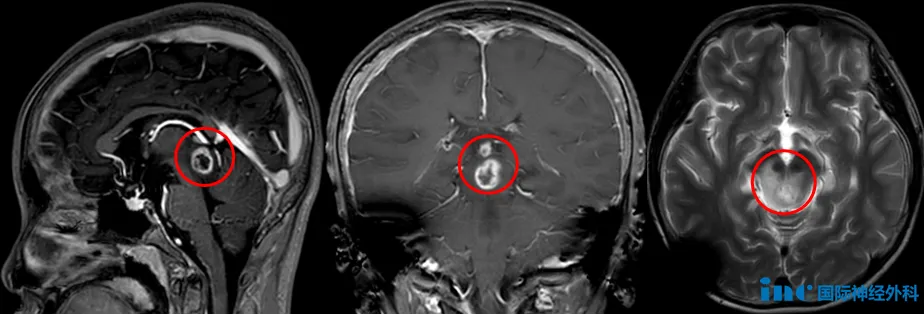

2024年11月,小泰父母发现孩子喝水时总会有水从左侧嘴角流出,笑起来时面部歪斜,而且右眼无法完全闭合,于是在观察了两三天后,决定带孩子去医院检查。这一查,就查出了问题。头颅CT显示了位于松果体区的不规则占位,医生怀疑为松果体生殖细胞肿瘤,且合并阻梗性脑积水。

“手术风险太大了,另一个医院的医生就建议我们去做伽马刀。”于是,小泰在12月开始接受伽马刀治疗。本以为不开颅就能消灭这个脑瘤,没想到仅3个月不到,复查时还是发现了近一半的肿瘤残余,而这部分逃过伽马刀狙击的肿瘤竟在四个月内悄悄生长着!

眼看着伽马刀失效,小泰父母陷入迷茫之中。他们来到北京寻求希望,医生得出的诊断为中脑顶盖星型细胞瘤可能性大,且周围正常组织在伽马刀后发生了坏死,建议再观察看看。

是的,可以进行手术切除,并且预后良好。当我切除肿瘤时,可以根据三个主要标准来判断,分别是肉眼所见、触感判断以及术中毫米尺。但需要说明的是,在MRI对比增强区域中,影像学上呈白色的部分并不一定完全都是肿瘤,可能还包含部分因放疗导致坏死(的组织),我认为我可以切除所有这些呈白色的部分。